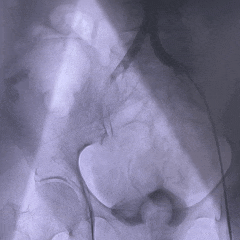

外周入路评估

外周血管内径充足,无明显钙化,腹主动脉轻微迂曲

47°非横位心